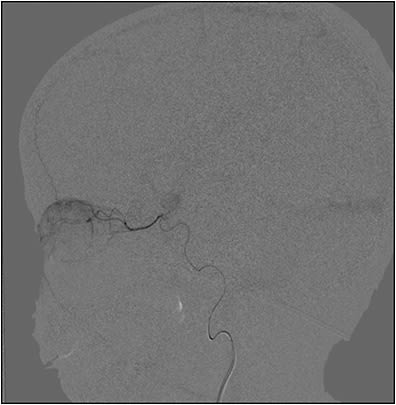

An experienced neurointerventional radiologist or endovascular neurosurgeon typically performs IAC for retinoblastoma under general anesthesia. The procedure can be performed in the outpatient or inpatient settings. Intravenous heparin is used for anticoagulation prior to the start of the procedure. Topical phenylephrine and intranasal vasoconstrictors may be used along the distribution of the supratrochlear artery to minimize chemotherapy delivery to the forehead and nose. The Seldinger technique is then used to access the ipsilateral femoral artery with a 4-French pediatric arterial sheath. Using fluoroscopy, the catheter is then guided to the ostium of the ophthalmic artery. Angiography is then performed to confirm the correct location and a patent ophthalmic artery vasculature, as well as to minimize any significant inadvertent reflux of dye into the cerebral circulation (Figure 1). Chemotherapeutic agents are then diluted in normal saline and manually injected slowly over 20-30 minutes in pulsatile fashion. After conclusion of the infusion, a repeat angiogram is performed to document a patent arterial flow and exclude a thromboembolic adverse event. If tandem IAC is performed, the catheter is then retracted to the level of the aorta and redirected to the contralateral internal carotid artery. It is important to note that the use of a guidewire should be avoided to minimize trauma to the ophthalmic artery. If the ophthalmic artery becomes sclerotic after multiple cycles or if it cannot be identified, the middle meningeal artery, a branch of the external carotid artery, may provide an alternative access to the ophthalmic artery.